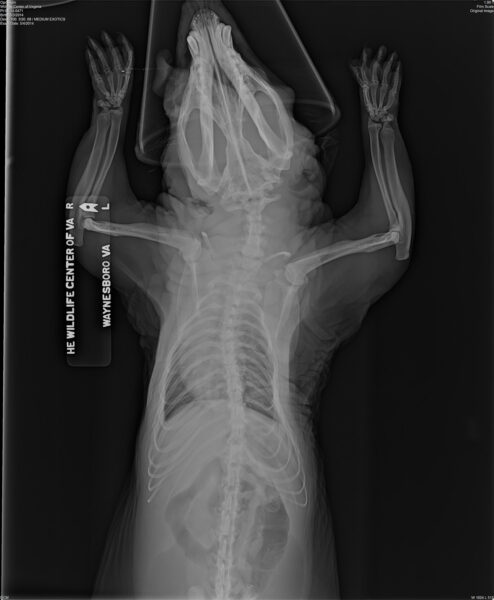

被拘留在囚禁的大鼠的 X 射線顯示了骨骼異常(腿部和脊椎的曲率),這種情況通常會發生在囚禁動物被未經訓練的人餵食不當時。由弗吉尼亞州野生動物中心提供